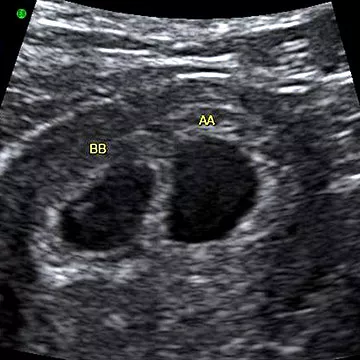

ورغم أن الأمر قد لا يبدو واضحًا كثيرًا، فإن هذه الدوائر تُظهر وجود كيسين حمليين منفصلين،وهذا يعني توأمًا!

أما في الحمل الواحد، يظهر كيس واحد فقط على الشاشة.

هنا، حدّد اختصاصي السونار (فني الموجات فوق الصوتية) كل جنين، أحدهما معلَّم بـ AA والآخر بـ BB.